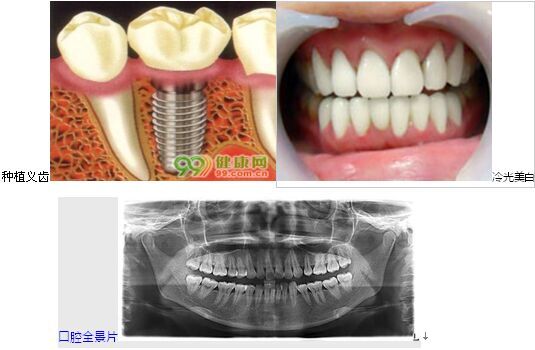

1.种植义齿:——缺牙修复的首选

种植义齿是在口腔缺牙区的牙槽骨内植入种植体(人工牙根),待种植体成活后,再在其上端制作修复体完成种植义齿的修复。它能显著地提高患者的咀嚼功能,且感觉舒适类似真牙,许多常规义齿难以解决的疑难修复临床病例通过种植义齿能得到满意疗效。不用磨除其他好牙齿,有助于防止牙槽骨吸收。

2.冷光美白——为你解决氟斑牙,四环素牙,烟渍色素黄牙的烦恼

冷光美白技术是将过氧化氢和直径为20um的二氧化硅为主的美白剂,快速产生氧化还原反应,美白剂通过牙本质小管,去除牙齿表面及深层沉着的色素,从而达到美白效果。快速美白,效果显著,无疼痛无刺激,不损害牙齿和牙龈。